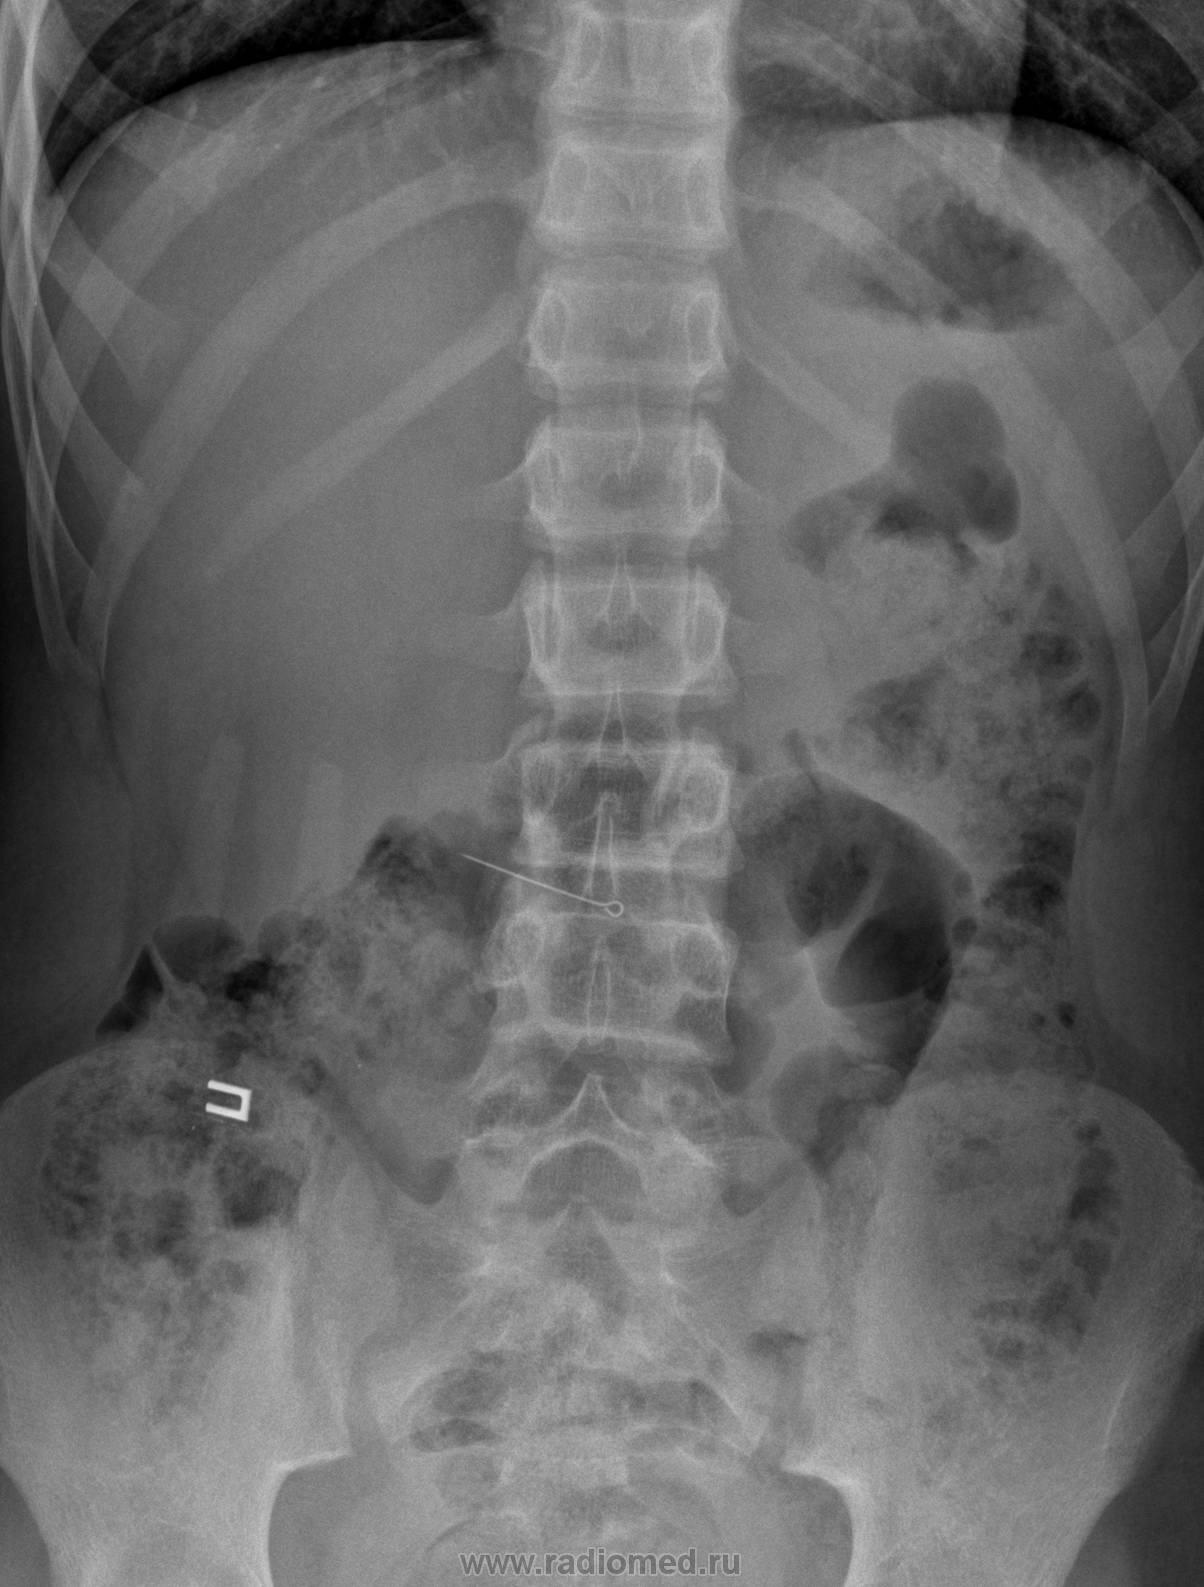

Пол пациента: Мужской пол Тип патологии: Другое Область исследования: Скелетно-мышечная система Методы исследования: Rg Ребёнок 13 лет проглатил булавку, каким образом... большой вопрос. Снимки сделаные сутки назад; А вот сегодня сделали в динамике: Признаков перфорации полого органа нет, поэтому хирурги решили выбрать выжидательную тактику. Пт, 11/09/2009 - 07:47 #1 OPEXOB Не на сайте Был на сайте: 9 лет 12 месяцев назад Зарегистрирован: 26.07.2008 - 10:02 Публикации: 280 Еще большой вопрос куда делась ушко у булавки? На первом снимке оно есть, на остальных, ?лизировано?. Пт, 11/09/2009 - 19:12 #2 Ola-la Не на сайте Был на сайте: 10 месяцев 2 недели назад Зарегистрирован: 06.12.2008 - 09:33 Публикации: 1786 Просто булавка так повернулась, что ушко не выделяется. https://www.instagram.com/pediatricradiology/ Пт, 11/09/2009 - 22:58 #3 Almo Не на сайте Был на сайте: 12 часов 43 минуты назад Зарегистрирован: 28.09.2008 - 18:50 Публикации: 8271 Конечно, булавка никак не может постянно быть в 1 положении( перисальтика и т.д....).

Конечно, булавка никак не может постянно быть в 1 положении( перисальтика и т.д....).